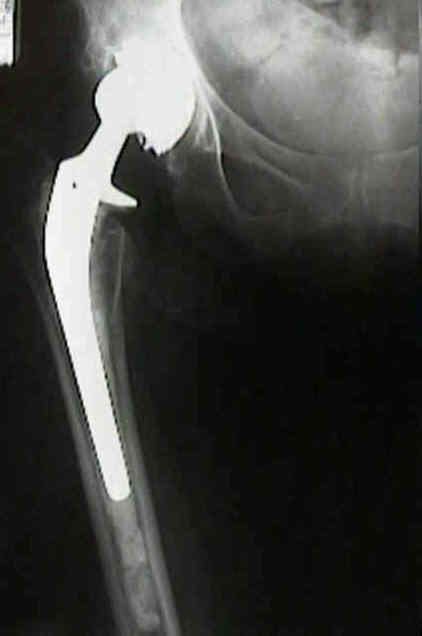

Loosening of Cemented Acetablar Components

(cemented acetabular component)

- radiolucency upto 2 mm wide with or without a surrounding fine line of density may develop in one or more of the the three zones about cement mass in the pelvis;

definite loosening

- migration of component of more than 5 mm;

- crack in cement mantle;

probable loosening

- continuous radiolucent line > 1-2 mm wide at the bone cement interface;

- as pointed out by Hodgkins et al 1988, the finding of a continuous radiolucent line about the acetabular component indicates loosening in 94% of patients;

Effect of Femoral Head Size

- higher frequency of isolated acetabular loosening was associated with use of a 32-mm femoral head.

- increased loosening rate of acetabulum w/ larger femoral head diameter may reflect thinner poly and higher frictional torsional stresses transmitted to the acetabular component;

- w/ smaller femoral heads, the frictional forces are less and the polyethylene is thicker